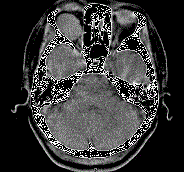

问题 41岁女性,右眼胀痛、眼球外突3月余,体检,发现低头时右侧眼球外突加重,CT检查如图所示,请选择最可能诊断 ( )

选项 A、右侧眶内神经鞘瘤 B、右侧眶内皮样囊肿 C、右侧眶内炎性假瘤 D、眼型格氏病 E、右侧眶内血管瘤

答案 E